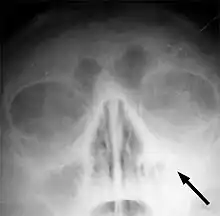

CT of chronic sinusitis

CT scan of chronic sinusitis, showing a filled right maxillary sinus with sclerotic thickened bone.